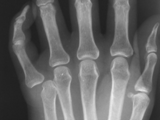

Gout-hand

Gout-hand